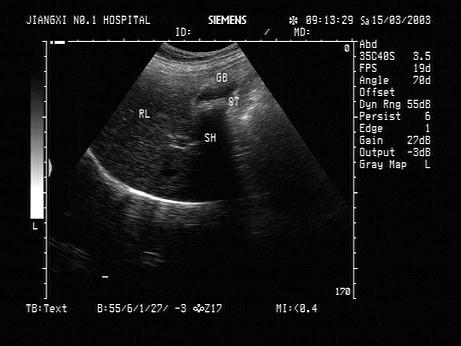

问题 女,42岁,反复上腹疼痛不适多年,加重3天。声像图如图所示,最可能的诊断为?(?)

选项 A.胆囊泥沙样结石 B.胆囊蛔虫 C.胆囊癌 D.胆囊息肉 E.胆汁淤积

答案 A